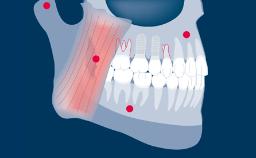

种植治疗已被证明是一种成功的治疗方式,它适用于广泛的牙齿修复临床适应症。虽然如此,但还是会出现并发症,有确凿的证据表明牙种植体的修复并发症发生率比天然牙齿高。这些并发症通常被称为“硬件并发症”,务必要了解它们的起因和最佳处理方式。本模块将对固定修复体的种植硬件并发症进行分类,然后根据分类阐明其不同的起因、最佳预防方法和处理方法。